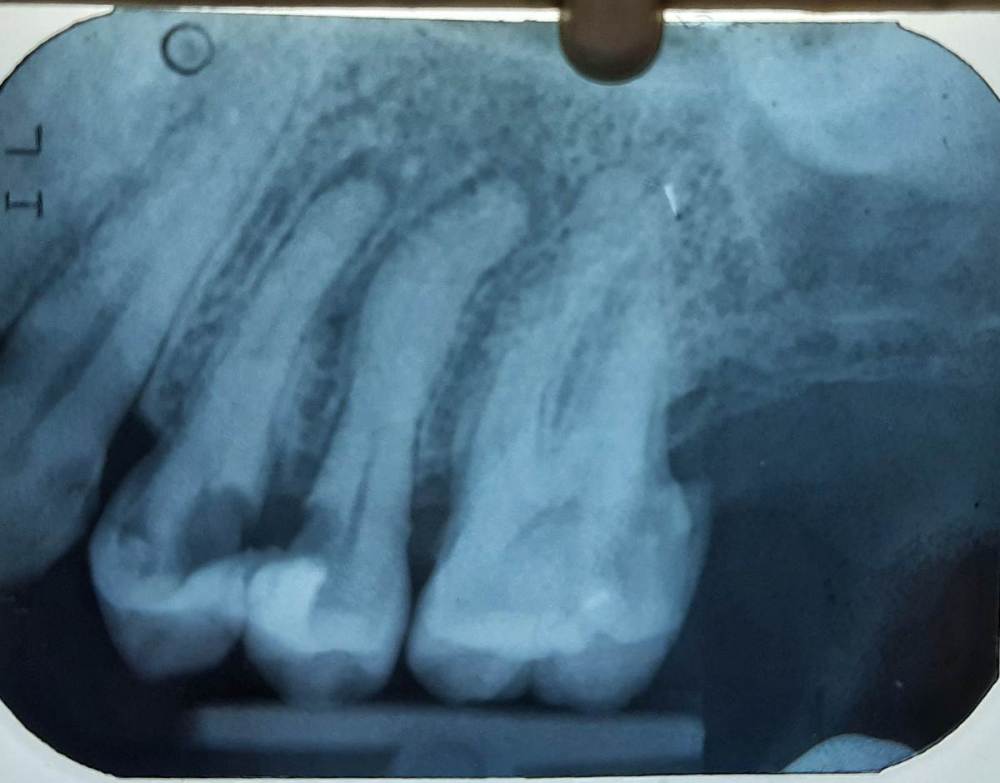

Lyubanya Опубликовано 7 июня, 2021 Поделиться Опубликовано 7 июня, 2021 Доброго времени суток, коллеги. Такой вопрос: зуб 24, 2 канала. В небном работаю на 20мм все ок, а щечный в самом конце болезненно(на 19мм), апекслокатор показывал out. Сделала анестезию, прошла канал, апекслокатор показал 0.2, на 21 мм. Работала ручными файлами, спустя время пациентка опять стала чувствовать:( Ирригация гипохлоритом, сушила пинами, крови нет. Почему так и что можно предпринять? Ссылка на комментарий